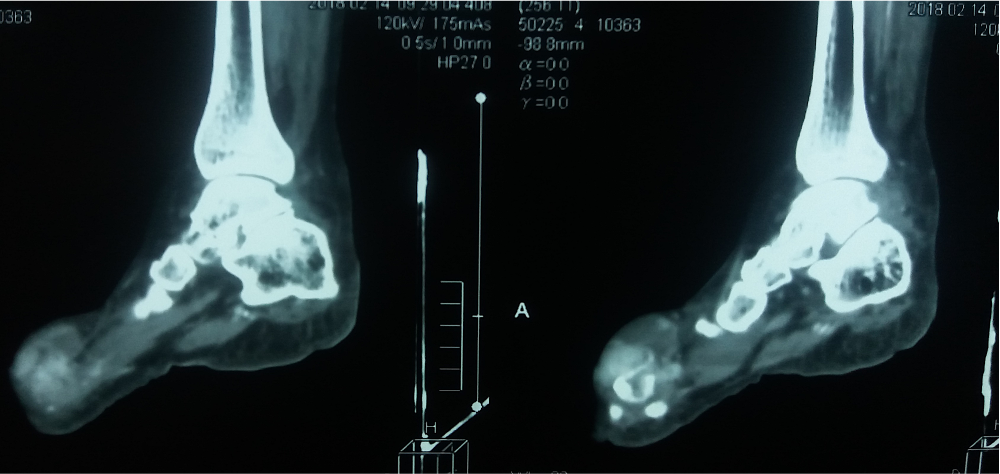

- Computed tomography (CT): same as plain radiographic findings

- Dual energy computed tomography (DECT):

- Tissue characterization and detection of urate is based on different attenuation of Xrays of variable energy in different tissues

- Only imaging technique that visualizes urate crystal depositions by their chemical composition

- Able to detect presence of dense urate crystal deposits even in small volumes

- Color coded images help in the clinical management of gout patients (Semin Arthritis Rheum 2014;43:662, Skeletal Radiol 2014;43:277)